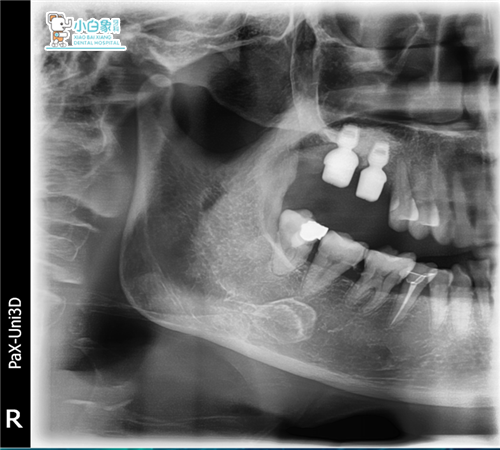

影像学检查:16 17见充填物影像。

治疗过程:16局麻下切龈翻瓣,内提升后置骨粉植入百康5*6植体一枚,严缝合。

17局麻下拔除,清理拔牙窝后内提升置骨粉植入百康5*6植体一枚,严密缝合。